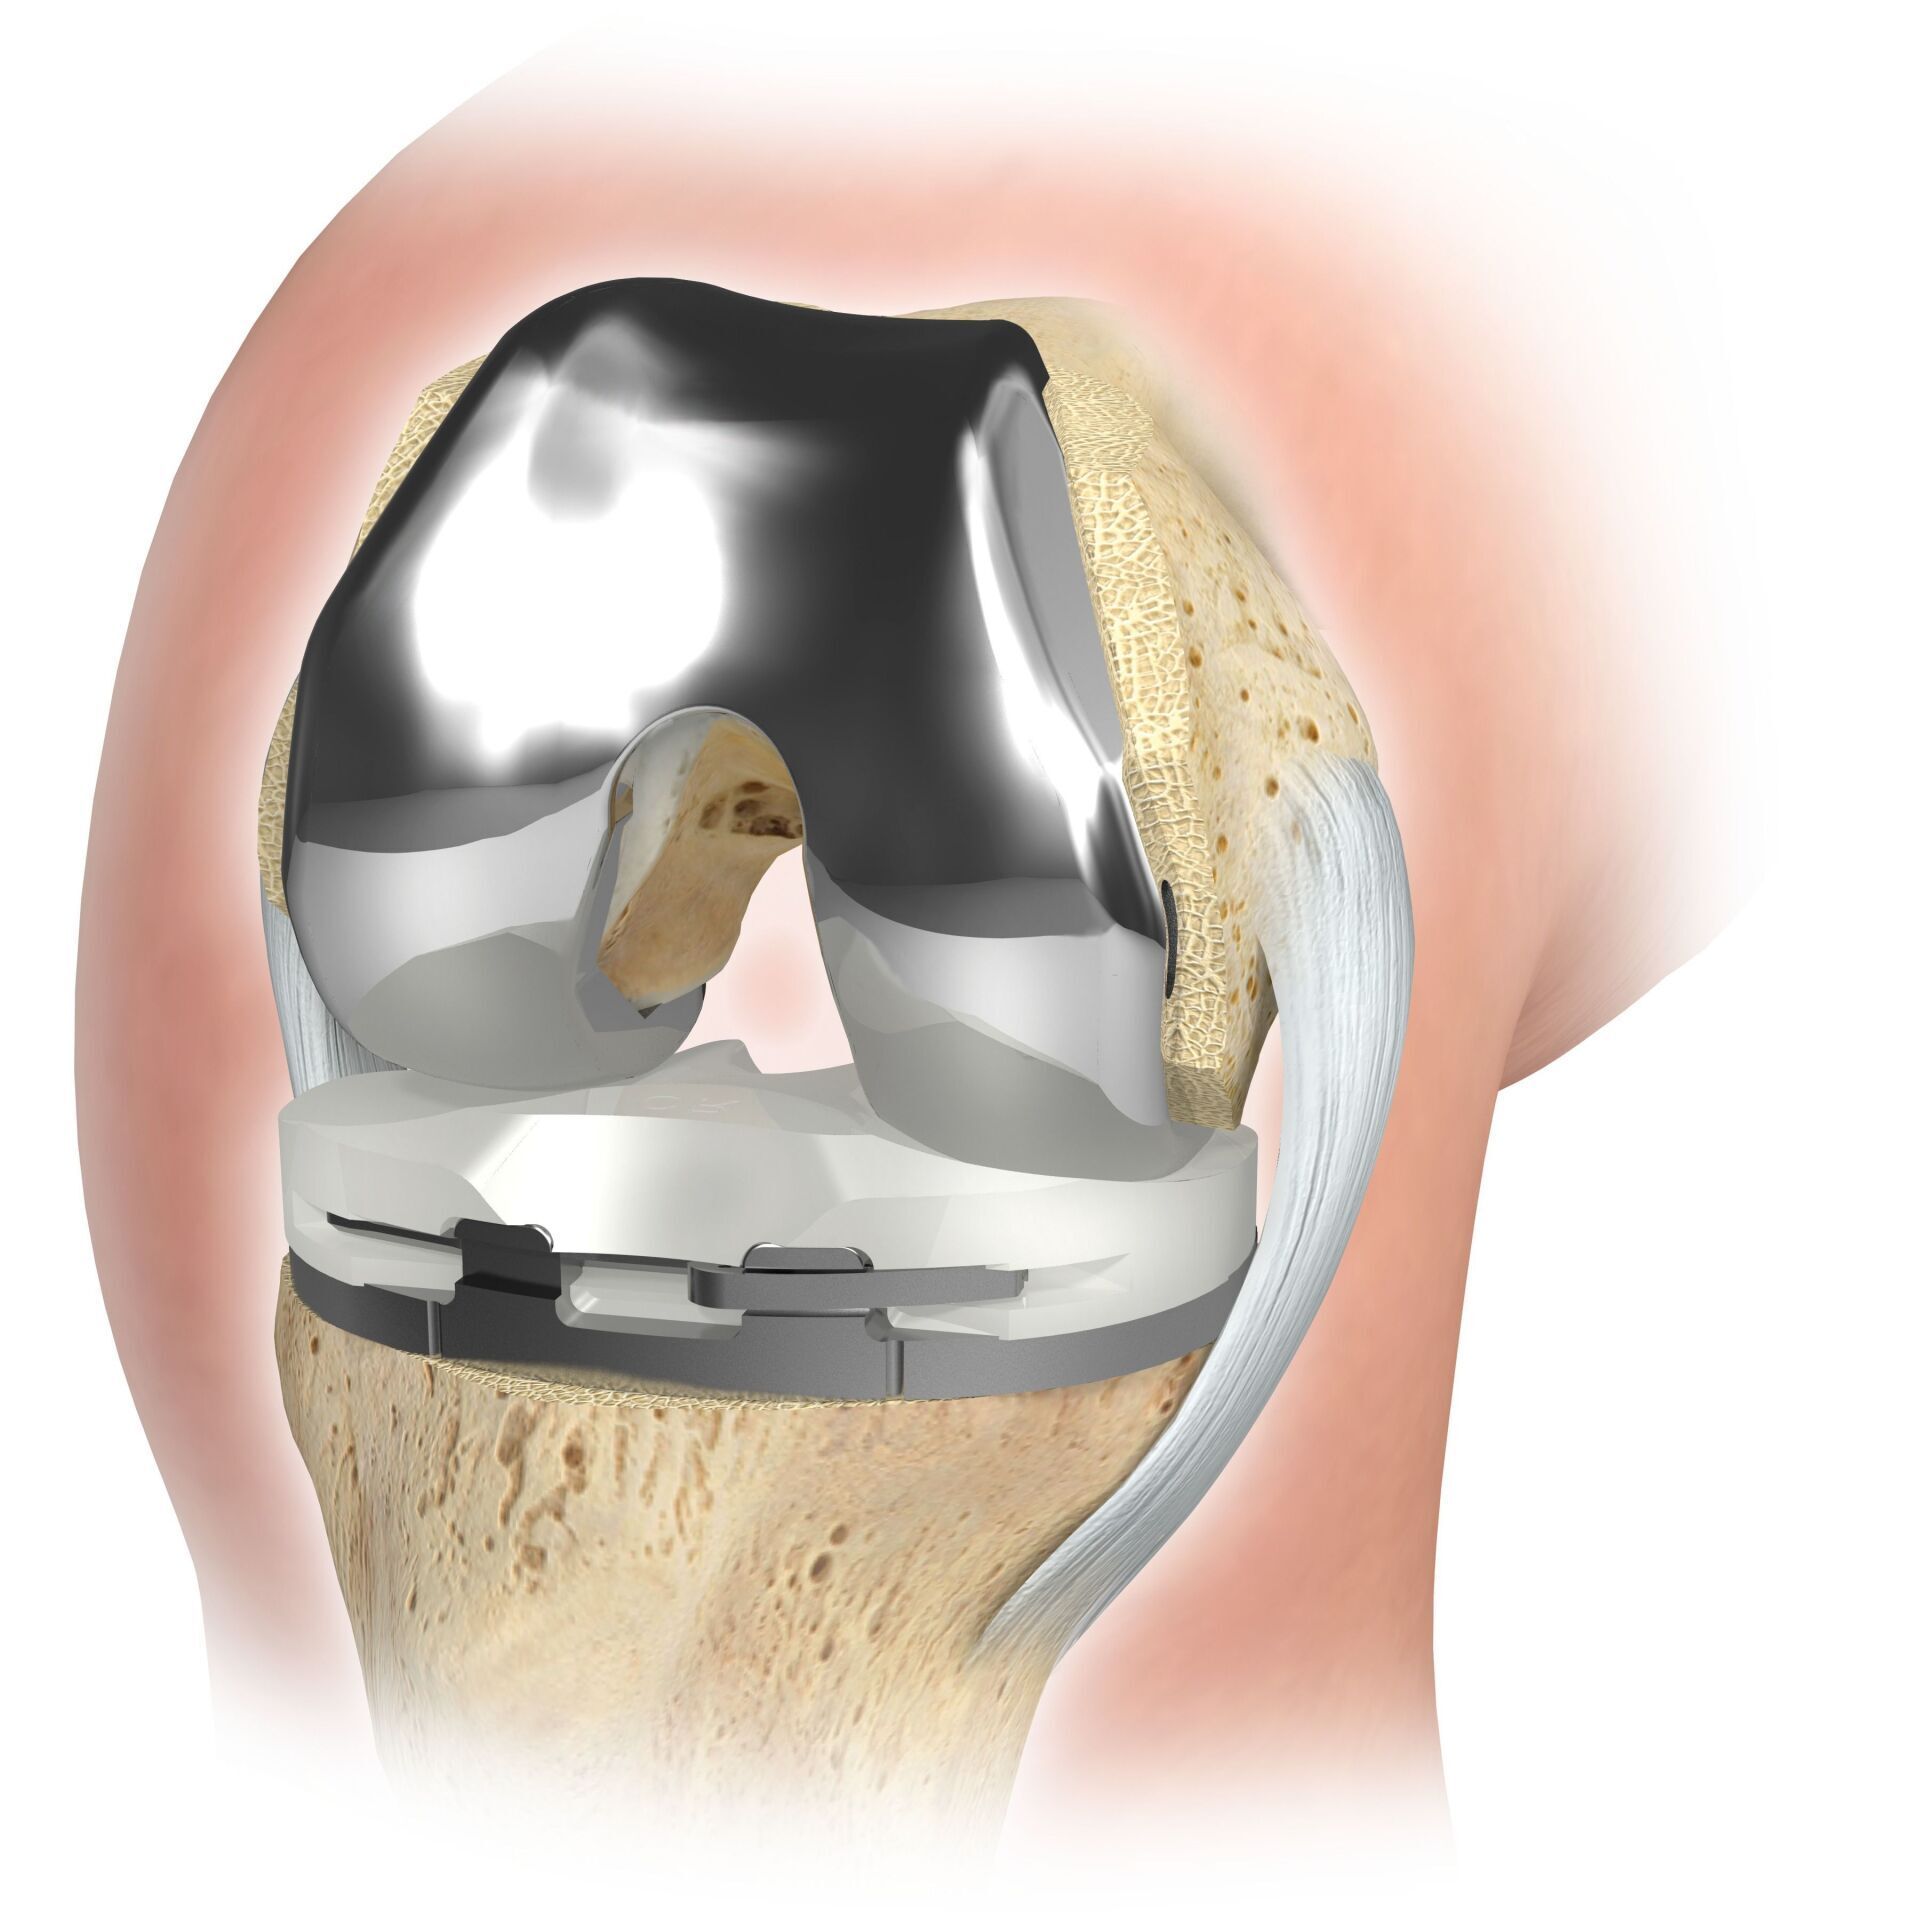

PTG (ARTICULATION ARTIFICIELLE DU GENOU)

L’articulation artificielle du genou remplace la surface cartilagineuse détruite par l’arthrose. L'os sous-jacent du fémur et de la tête tibiale reste intact. Certains comparent une articulation artificielle moderne du genou à un couronnement de dent ; le terme exact est ce qu'on appelle le resurfaçage bicondylien. Entre les nouvelles surfaces sur la partie supérieure et inférieure de la jambe se trouve ce que l'on appelle une incrustation en plastique blanc spécialement durci, qui peut être vue sur l'image radiographique comme la distance entre les pièces métalliques.

- Arthroplastie partielle cimentée ou sans ciment par prothèses à glissière (internes ou externes) Arthroplastie partielle cimentée par prothèse PFJ ou Wave (remplacement de la surface rotulienne) Arthroplastie complète cimentée (classique : la « prothèse du genou ») EXTRA Implants stabilisants ou guidés par axe prothèses INLAYS comme remplacement du ménisque en polyéthylène hautement réseauté

Pendant l'opération, l'articulation du genou est accessible par l'avant et le genou est plié et étendu plusieurs fois pendant l'opération. Les ligaments externes et internes et, dans certains cas, les ligaments croisés sont soigneusement protégés pendant l'opération.